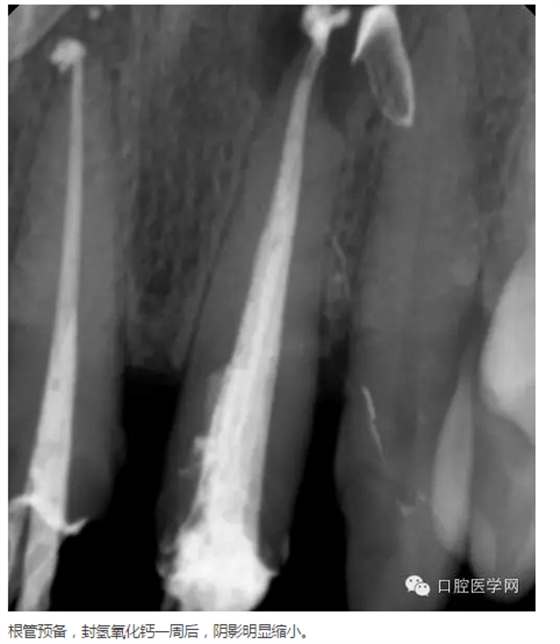

治療方案:建議拆除牙冠,21行根管治療,樁核、全冠修復(fù)